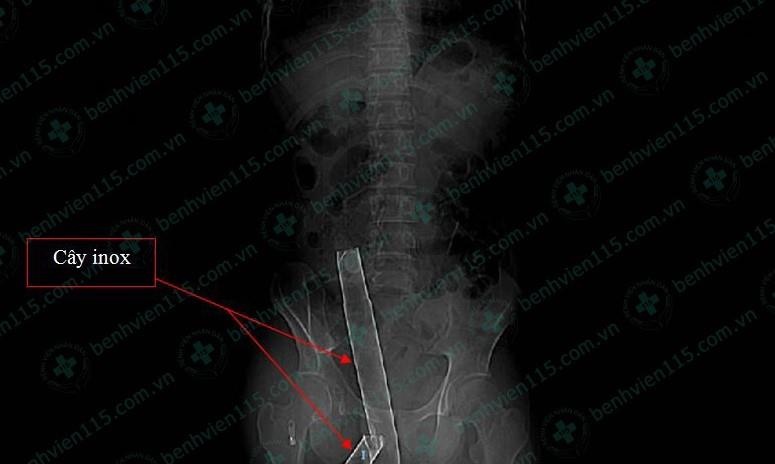

| Hình ảnh thanh inox đâm xuyên từ mông và bụng bệnh nhân. Ảnh: BVCC. |

Tại đây, bệnh nhân được truyền dịch, chống sốc và thực hiện các cận lâm sàng cần thiết. Kết quả chụp CT ghi nhận người này bị dị vật kim loại đâm từ giữa mông, xuyên ra ngoài giữa nhóm cơ dựng sống và cơ thắt lưng chậu bên, vào tận cùng mỏm ngang L2 bên phải.

Cây inox được lấy ra ngoài có chiều dài 1,1 m, đường kính 3 cm, đoạn xuyên thấu vào cơ thể bệnh nhân dài khoảng 25 cm.